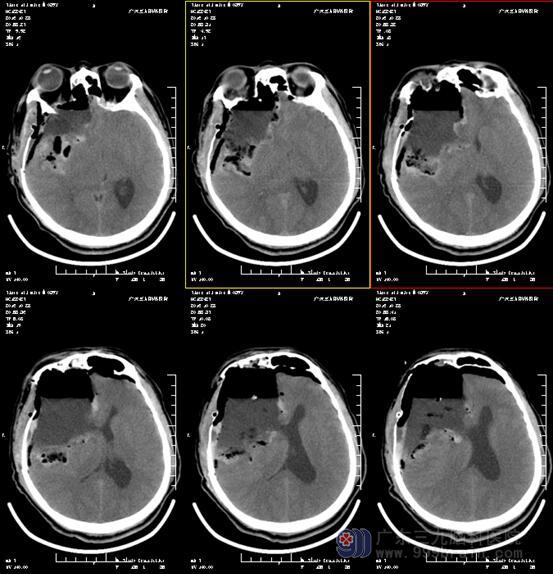

图4:术后4小时CT显示术后改变,肿瘤全切,未见钙化,留下巨大手术腔

少突胶质细胞瘤以手术治疗为主,术后平均生存期为3-5年,辅以放疗和(或)化疗,以防肿瘤复发或者残存肿瘤增大。本例患者为WHO II级,低度恶性,术后肿瘤全切,予以继续行放疗,目前进一步随访中。